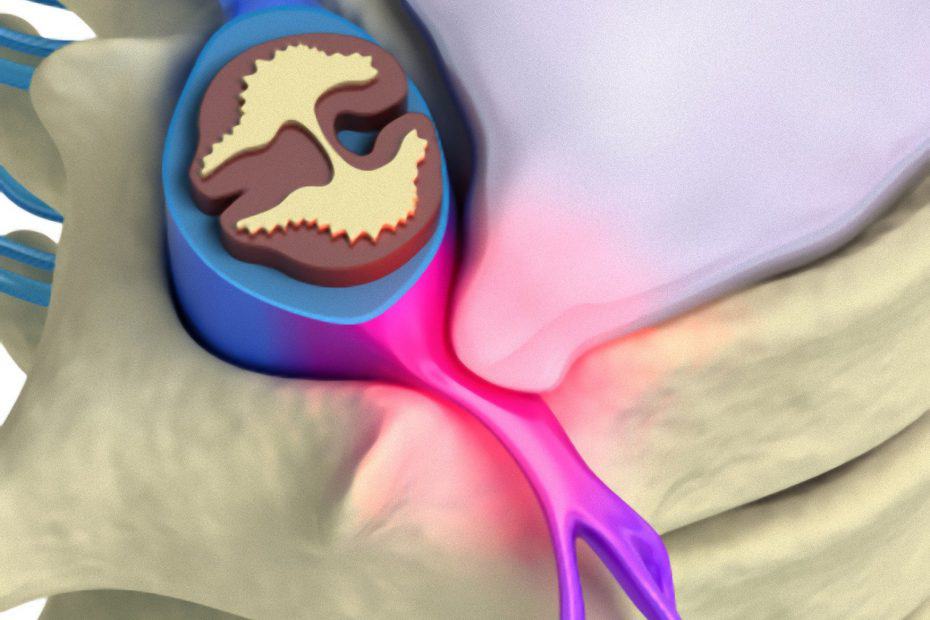

Cistos colóides são lesões benignas que constituem cerca de 1% de todos os tumores intracranianos. Tipicamente estão localizados nos ventrículos cerebrais, que são bolsões onde… Read More »Endoscopia Cerebral – Cisto Colóide